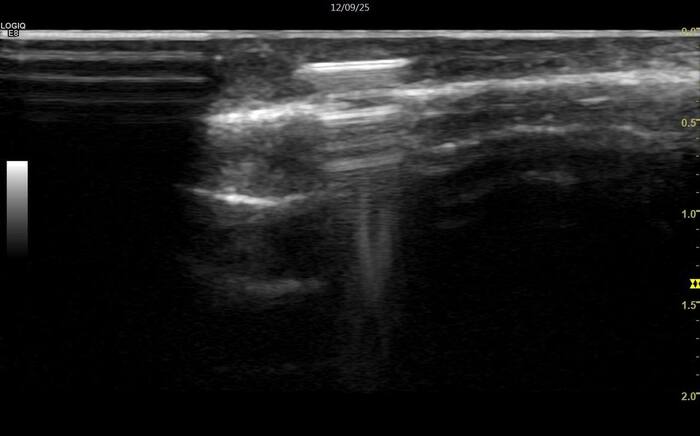

Для убедительности все же лучше получить инструментальное подтверждение, УЗИ для этого прекрасно подойдет, с его помощью можно оценить наличие воспаления, состояние связочного аппарата.